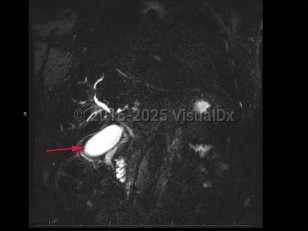

Cirrhosis, hepatitis B, hepatitis C, primary sclerosing cholangitis, and hepatobiliary flukes are known risk factors for cholangiocarcinoma. However, most cholangiocarcinomas develop in patients with no identifiable risk factors. It is a rare childhood malignancy. Incidence is highest in Hispanic and Asian populations.

Patients with cholangiocarcinoma will often have elevations in their liver function tests (total and direct bilirubin) and liver enzymes (aspartate transaminase [AST], alanine transaminase [ALT], alkaline phosphatase), although these are nonspecific findings. Elevations in cancer antigen (CA) 19-9, a tumor marker, can be suggestive of cholangiocarcinoma but are limited by nonspecificity. Diagnosis typically requires tissue sampling via endoscopic retrograde cholangiopancreatography (ERCP) with brushing.